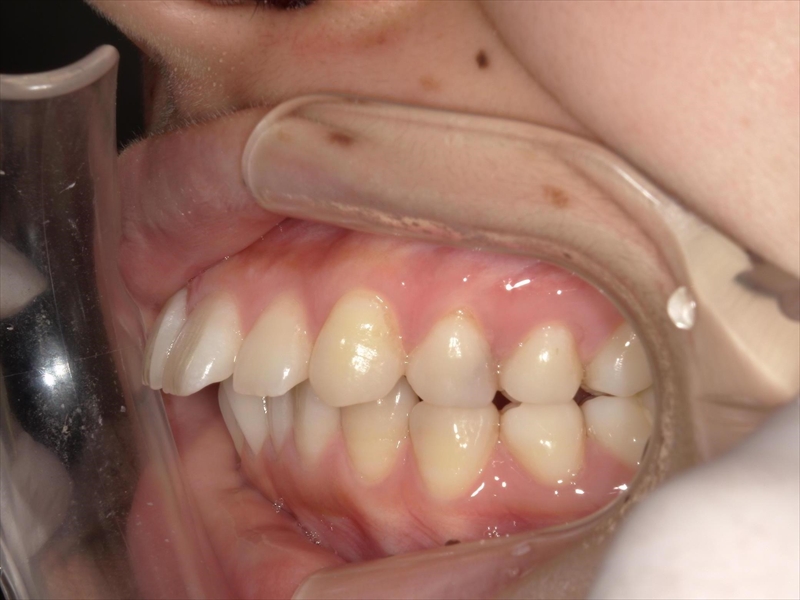

この患者様は、重度の出っ歯があり、下顎前歯には叢生が認められました。

また、奥歯の噛み合わせにも問題があり、本来は半歯分ずつずれて噛み合うべきところが、正しく機能していない状態でした。

その影響で咀嚼力は一般成人の約半分程度に低下しており、顎関節症の疑いもありました。

前歯を収めるスペースを確保するために歯を削り(IPR)、奥歯から順に後方(奥)へ下げる並びを整える計画を立案いたしました。